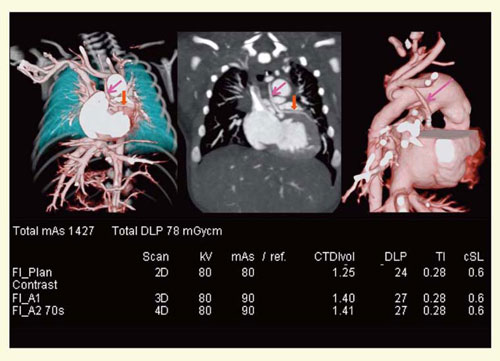

œ Ç—á1F¶S’áŒ`¬ÇŒóŒQi}3j

0Î3“úC’jŽ™C‘Ìd3270gCS””132bpmB“ú—î1“ú‚É’´‰¹”gŒŸ¸‚ŶS’áŒ`¬ÇŒóŒQ‚ª‹^‚í‚êC“ú—î2“ú‚É“–‰@‚Ö”À‘—‚³‚ꂽBp‘OŒ`‘Ôf’f‚Ì‚½‚ßC“ú—î3“ú‚É‘¢‰eCT‚ªŽ{s‚³‚ꂽB”ñí‚Éׂ¢ãs`‹|•”‘å“®–¬‚ÆCãs‘å“®–¬Šî•”‚©‚番Šò‚·‚銥“®–¬‚ª–¾—Ăɕ`o‚³‚ê‚Ä‚¢‚éBгޙ‚Ìó‘Ô‚ªˆ«‚C–³’ÁÂɂĎB‰e‚µ‚½B

}3@Ç—á1F¶S’áŒ`¬ÇŒóŒQi0Î3“úC’jŽ™j

œ Ç—á2Fƒtƒ@ƒ[Žl’¥ÇC‰Emodified BT shuntpŒãi}4j

1Î1‚©ŒŽC’jŽ™C‘Ìd8kgCS””100bpmBS“àC•œp‘O‚É‘–s‚ðŠm”F‚·‚é–Ú“I‚ÅCT‚ªŽB‰e‚³‚ꂽBŠ¥“®–¬isingle coronary arteryj‚ª•`o‚³‚ê‚Ä‚¢‚éB‘å“®–¬Šî•”‘O•Ç‚©‚çconus brunch‚Æl‚¦‚ç‚ê‚镪Ž}‚ª’¼Ú•ªŠò‚µ‚Ä‚¢‚邪CpŽ®‚ɂ͉e‹¿‚È‚µ‚Æ”»’f‚³‚êC—‚“úC—\’è’Ê‚èŽèp‚ªŽ{s‚³‚ꂽB

}4@Ç—á2Fƒtƒ@ƒ[Žl’¥Çi1Î1‚©ŒŽC’jŽ™j

œ Ç—á3Fìè•aŒãŠ¥“®–¬áŽi}5j

3Î11‚©ŒŽC’jŽ™C‘Ìd11kgCS””102bpmB•·‚«•ª‚¯‚ª‚È‚’ÁÂð—v‚µ‚½‚ªCŠO—ˆŒŸ¸‚Ì‚½‚ߌy“x‚Ì’ÁÃEŠoÁ‰ºEŒÄ‹z’âŽ~•s‰Â”\‚Å‚ ‚Á‚½B‚±‚Ì‚½‚ßS“d}”ñ“¯ŠúCFlash Spiral‚ɂĎB‰e‚µ‚½B ¶Š¥“®–¬•ªŠò•”‚ÉŠ¥“®–¬áŽ‚ª–¾—Ăɕ`o‚³‚ê‚Ä‚¢‚éB

}5@Ç—á3Fìè•aŒãŠ¥“®–¬áŽi3Î11‚©ŒŽC’jŽ™j

œ Ç—á4F‘å“®–¬—£’fÇi}6j

0Î1‚©ŒŽC’jŽ™C‘Ìd4kgCS””140bpmB’´‰¹”gŒŸ¸‚ɂđ哮–¬kóÇ‚ª‹^‚í‚êCp‘O‚É‘¢‰eCT‚ªŽ{s‚³‚ꂽB¶½œ‰º“®–¬•ªŠò’¼‘O‚ÅC‘å“®–¬‹|‚ª“r₵‚Ä‚¨‚èC‘å“®–¬—£’fÇ‚Æf’f‚³‚ꂽB

}6@Ç—á4F‘å“®–¬—£’fÇi0Î1‚©ŒŽC’jŽ™j